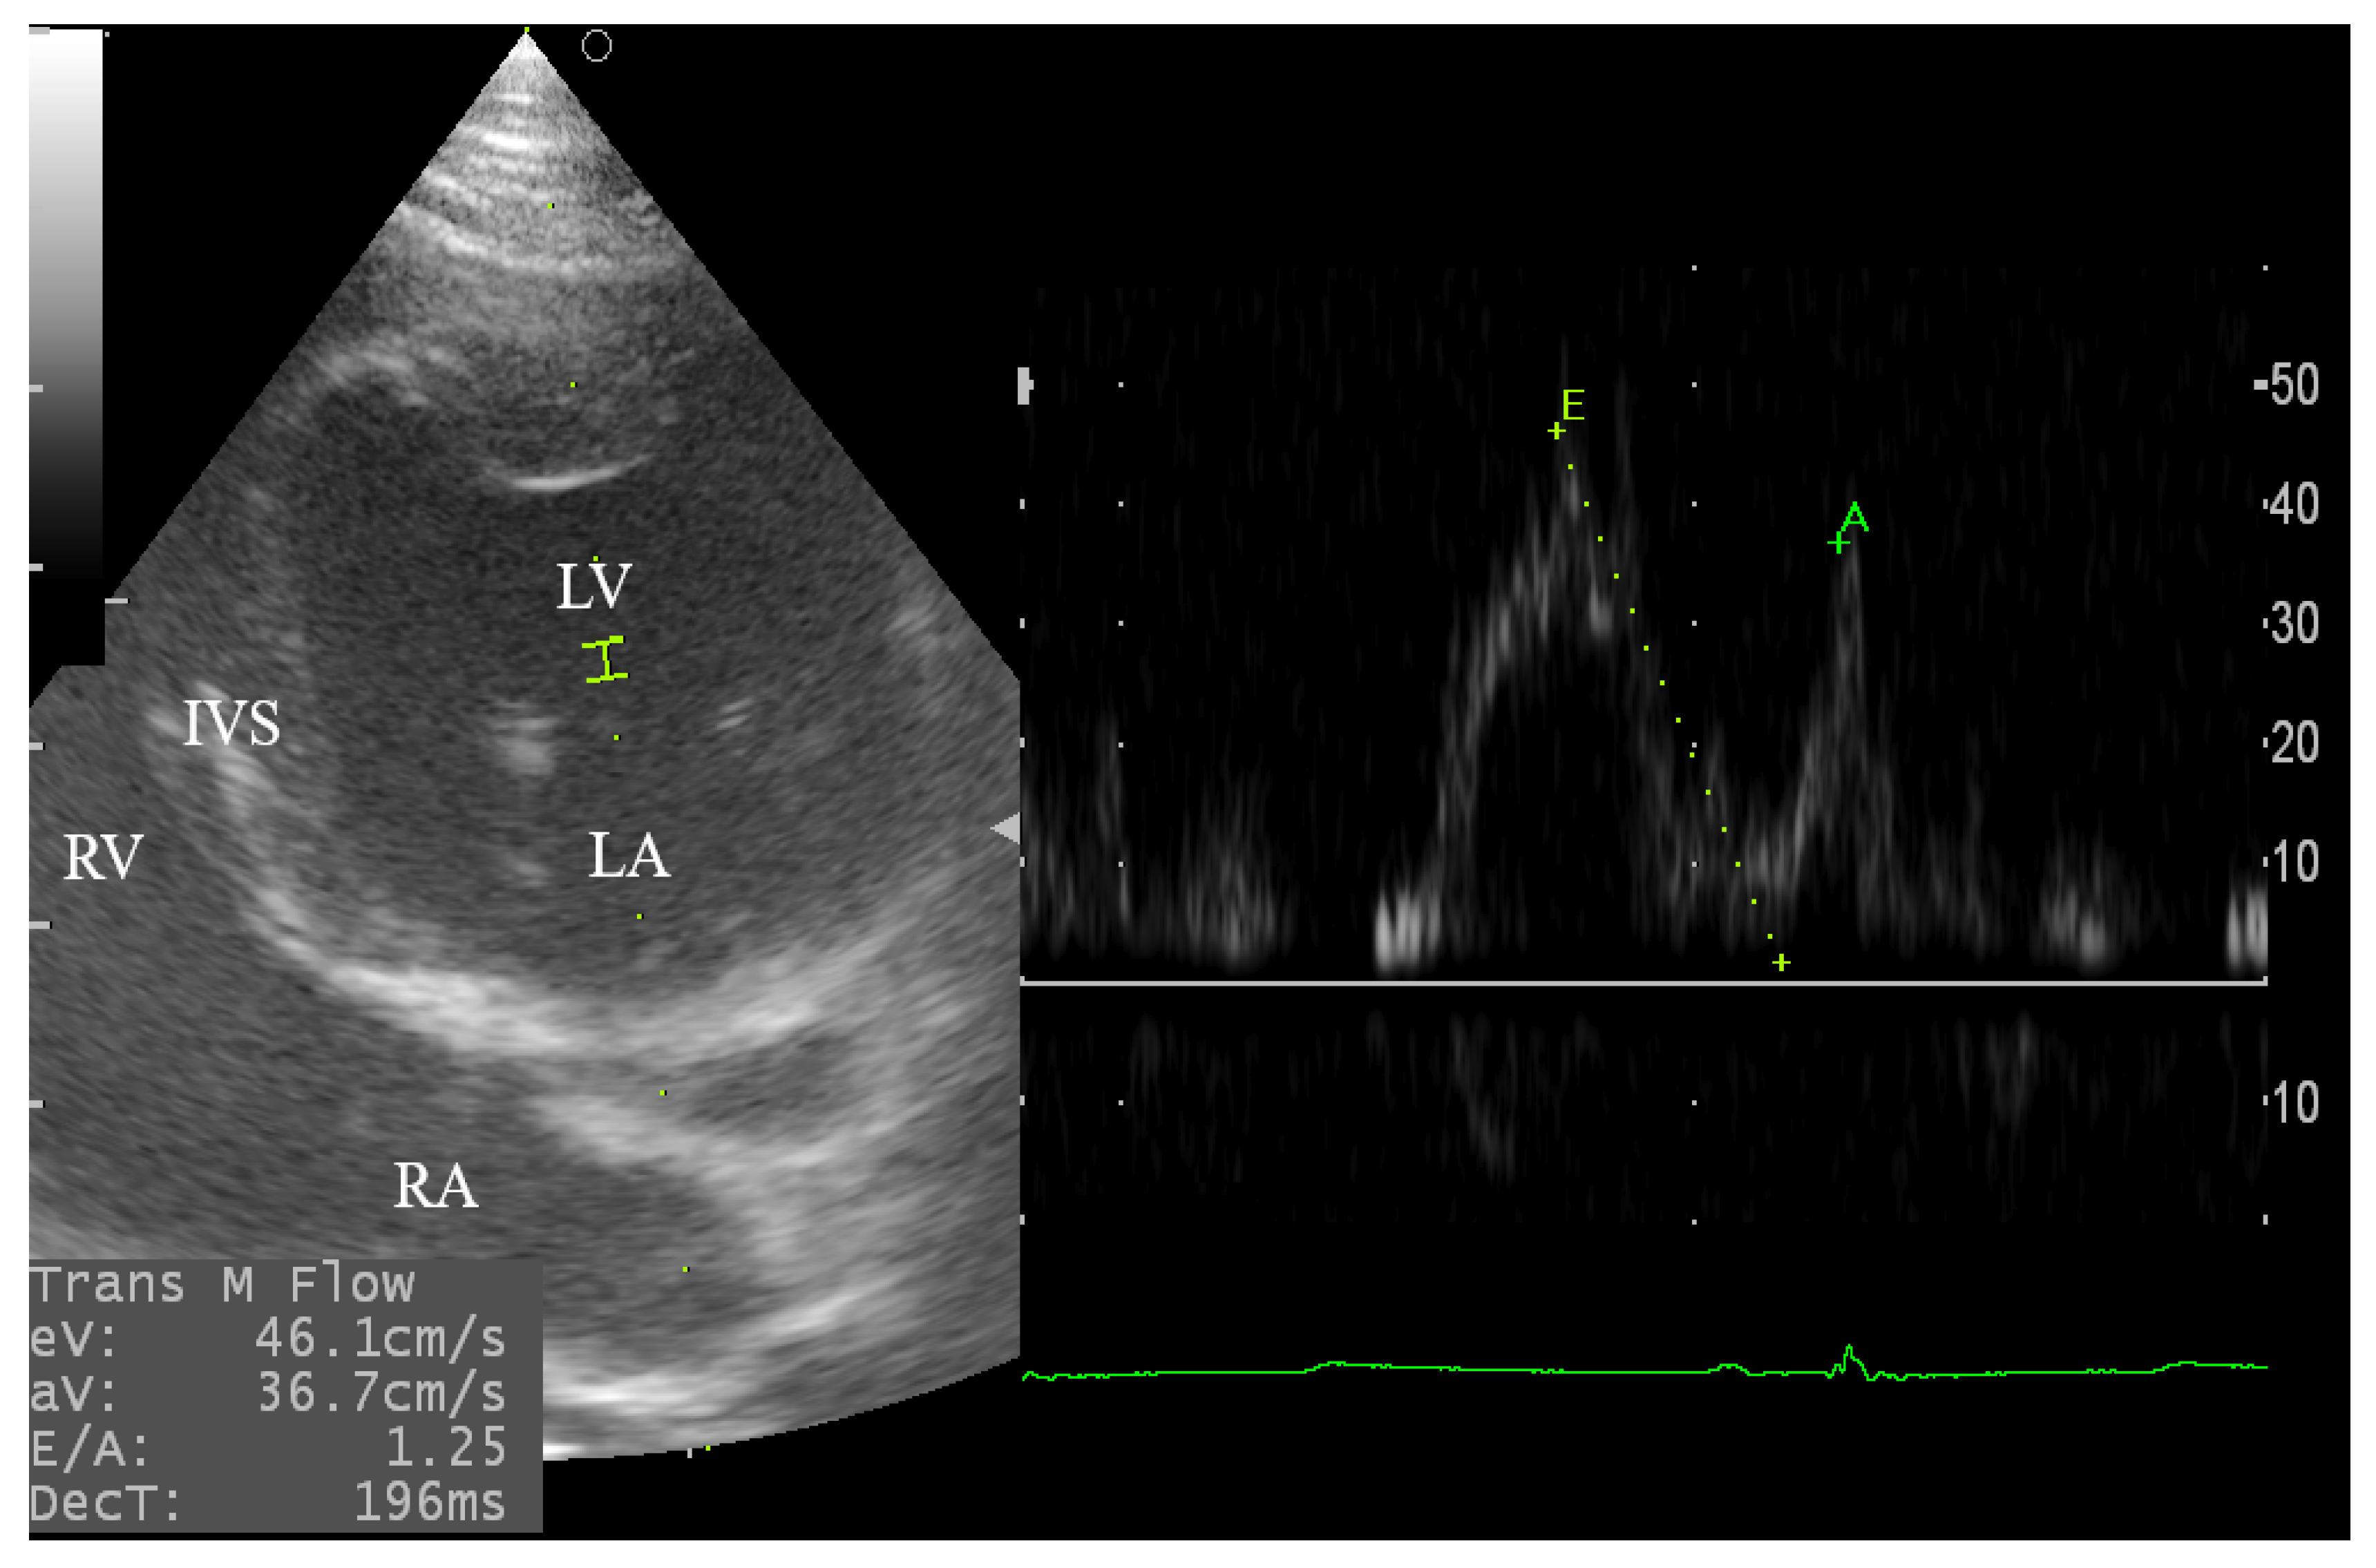

3.4.1. Assessment of the Aortic and Mitral Blood Flow

| Mitral inflow | Ev | cm/s | 48.71 | 8.872 | >0.10 | ns | 18.21 |

| Av | cm/s | 52.08 | 9.816 | >0.10 | ns | 18.85 | |

| E/A | 0.944 | 0.196 | >0.10 | ns | 20.78 | ||

| DecT | ms | 126.9 | 26.41 | >0.10 | ns | 20.81 | |

| Mitral inflow | ||||

| Ev | cm/s | 55.2 ± 3.6 | 45.8 ± 2.4 | 0.05 * |

| Av | cm/s | 52.4 ± 4.1 | 39.1 ± 2.4 | 0.01 * |

| E/A | 1.0 ± 0.1 | 1.2 ± 0.1 | 0.15 | |

| DecT | ms | 106.5 ± 13.4 | 163.4 ± 15.2 | 0.02 * |